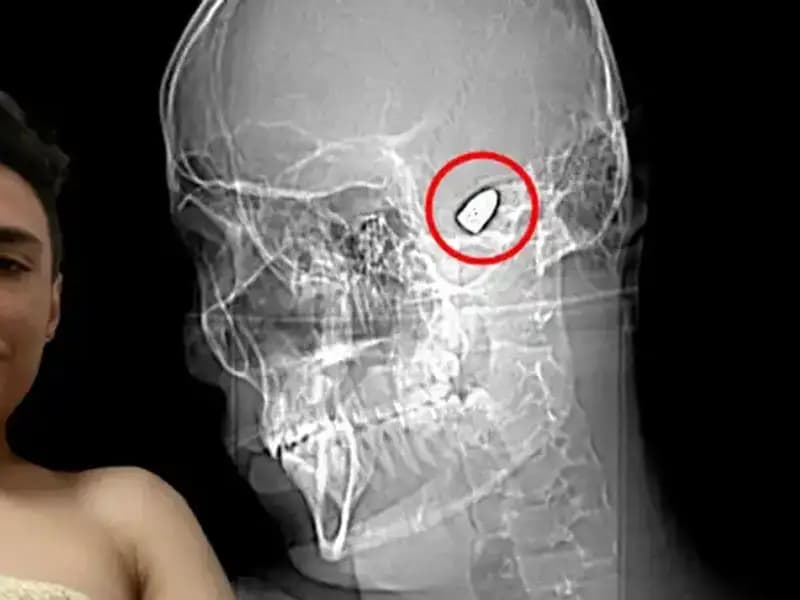

Bu cesur adam, sıradan bir hayata dalıp gidebilecek bir insan gibi görünüyordu. Ancak yaşadığı kaza sonrası hayatı bir anda tersine döndü. Günün birinde, başına gelen talihsiz bir olay nedeniyle kafasında patlayıcı bir düzenekle yaşamak zorunda kaldı. Bu durum, sıradan bir hayat süren insanın, beklenmedik bir şekilde bir "kurtuluş" savaşı vermesine neden oldu. Patlayıcının yerleşimi, onun günlük yaşamına derin etkiler bıraktı; bu sadece fiziksel değil, ruhsal boyutta da büyük bir travma yarattı.

Her gün, hayatının her anında bu tehlikeli düzenekle yaşamak zorunda olan adam, kendini her an "biter-hazır" mode içerisinde hissediyor. Patlayıcıyı kontrol altında tutmak, sadece zihinsel bir zorluk değil, aynı zamanda sosyal ilişkilerini de etkileyen bir durum haline geldi. Arkadaşları, ailesi ve çevresindekiler, onun yaşamını sürdürme çabasını desteklemek yerine, korku ve kaygıyla doldu. Kendine bir çıkış yolu arayışındaki bu adam, ruhen de ciddi bir mücadele vermek zorunda kaldı.